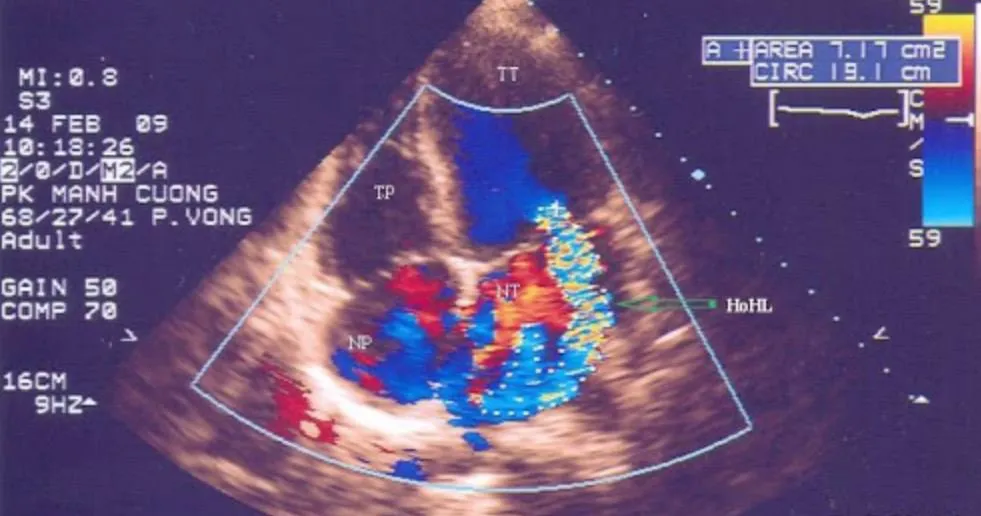

2.1. Siêu âm Doppler màu

• Siêu âm tim hở van 2 lá bằng phương pháp siêu âm Doppler màu được sử dụng rộng rãi để chẩn đoán xác định và đánh giá mức độ hở van lá. Hở van 2 lá trên siêu âm Doppler được chia làm 4 độ từ 1/4 đến 4/4. Hoặc cũng có thể đánh giá bằng các mức độ từ nhẹ (1+), vừa (2+), nhiều (3+) và rất nhiều (4+). Siêu âm Doppler màu giúp nhìn thấy được hình ảnh dòng màu phụt ngược về nhĩ trái. Dựa vào sự lan của dòng màu phụt ngược có thể ước tính độ hở của van 2 lá. Để đánh giá cụ thể hơn mức độ hở của van, có thể dựa vào các thông số như:

• Độ dài tối đa của dòng màu phụt ngược trong nhĩ trái.

• Tỷ lệ diện tích dòng hở so với diện tích nhĩ trái.

• Phương pháp này chính xác đối với hở van hai lá kiểu trung tâm, tuy nhiên đối với những dòng hở lệch tâm lớn, hở van 2 lá cần được tính tăng thêm 1 độ. Khi sử dụng siêu âm tim đánh giá hở van hai lá, cần chú ý các yếu tố có thể ảnh hưởng đến độ chính xác như: